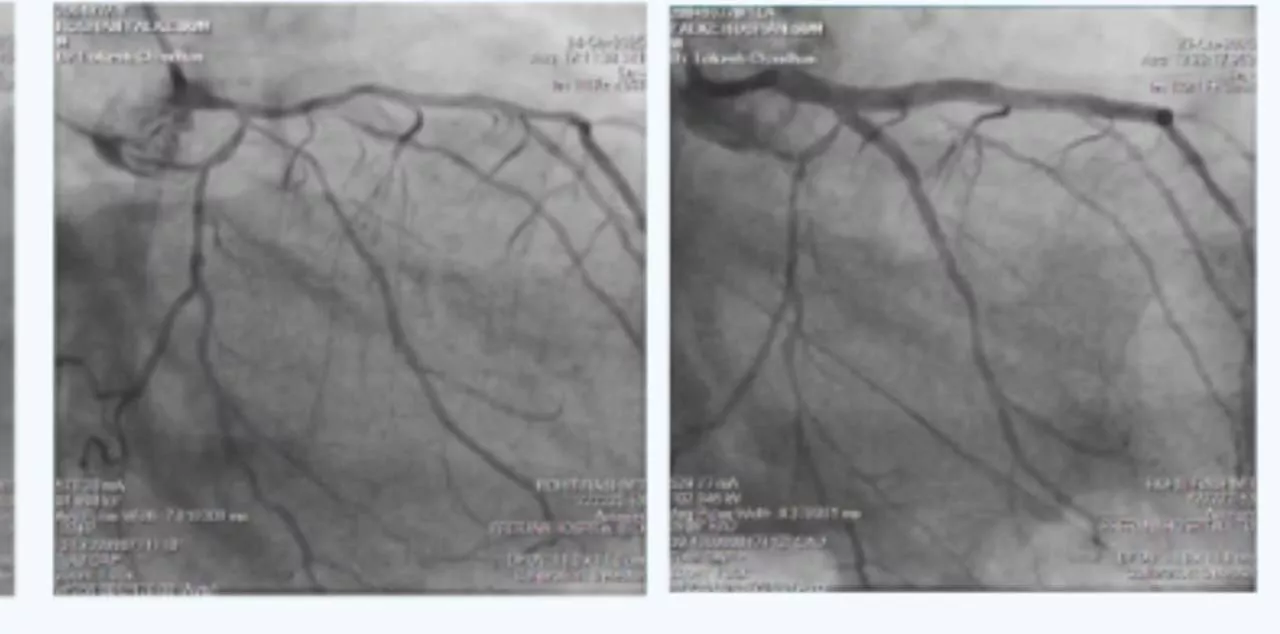

The Department of Cardiothoracic Surgery deals with the surgical management of diseases related to heart, lungs, chest wall and diaphragm. Our competent team is highly experienced in performing complicated surgeries for conditions such as congenital heart diseases, mediastinal tumours, open heart valvular repairs, and myocardial infarction.